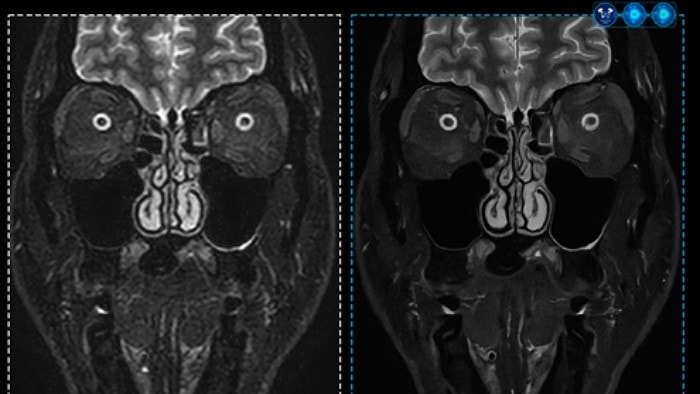

SmartSpeed Precise integrates a dual AI engine to Philips’ MR acceleration technology "Compressed SENSE," improving both scanning speed and image quality. Working from the raw data stage, a data-balancing algorithm and proprietary AI reconstruction algorithm filter essential signals while eliminating unnecessary noise during repeated reconstruction.

By combining enhanced ‘Super Resolution Algorithms’ and dual AI engines, the technology improves image resolution and signal-to-noise ratio (SNR), enhances anti-ringing features, and increases sharpness by up to 80%. This dual AI-based image reconstruction delivers scanning up to three times faster and significantly improved image quality compared to conventional methods. It supports all anatomical areas and is compatible with 97% of MR protocols, including 2D, 3D, and 4D scanning.